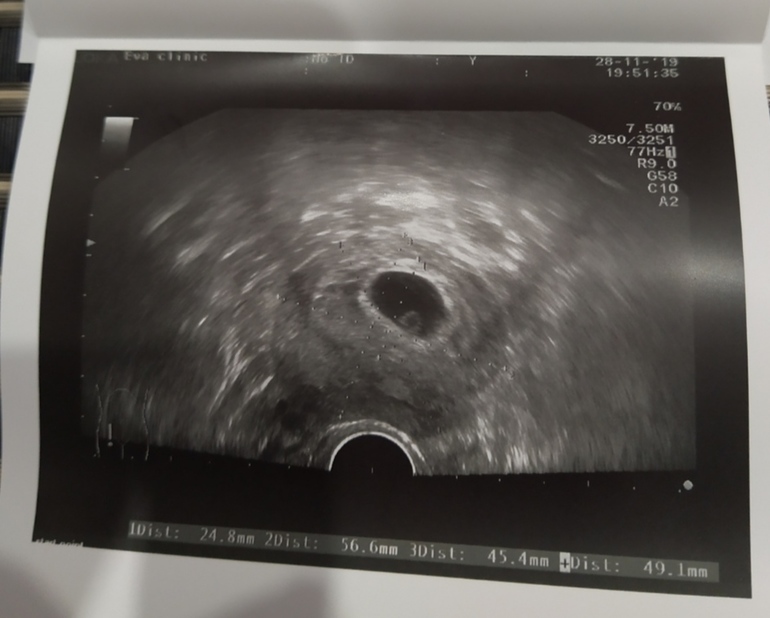

В овуляции точно уверена,она была 26 октября,на 14 д.ц, единственный па на 12 д.ц,в 5 недель ровно пя было 7 мм и больше ничего,вчера в 6+5 пя 20 мм(прилично выросло) жм 5 мм и пусто(((

Я пошла узи смотрела, у меня внутренний размер пя 20мм, и эмбрион в дневнике глянь, там точечка! Чуть слабее аппаратура и все! Никакого эмбриона там нет!